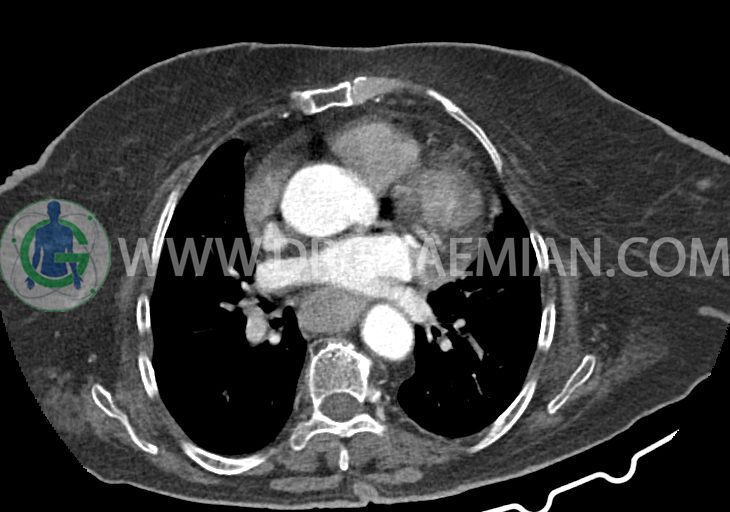

در سی تی اسکن اسپیرال ریه و مدیاستن – شکم و لگن با و بدون کنتراست خوراکی و وریدی (مولتی دیدکتور 16 با مقاطع ظریف و بازسازی های ساژیتال و کرونال):

–کاردیومگالی همراه با pericardial effusion خفیف

–یک ندول به ابعاد 19x18mm با حدود اسپیلوکه در سگمان لترال RML و دو ندول کوچکتر در مجاورت فوقانی آن به اقطار 6mm و 5mm ( مطرح کننده کارسینوم برونکوژنیک یا متاستاز )

–دیلاتاسیون نیمه فوقانی مری توراسیک ناشی از افزایش ضخامت circumferential توده مانند در یک سوم دیستال مری به طول 50mm ، که می تواند مطرح کننده انفیلتراسیون تومورال همراه با تنگی

–آئورت صعودی دیلاته به قطر 38mm